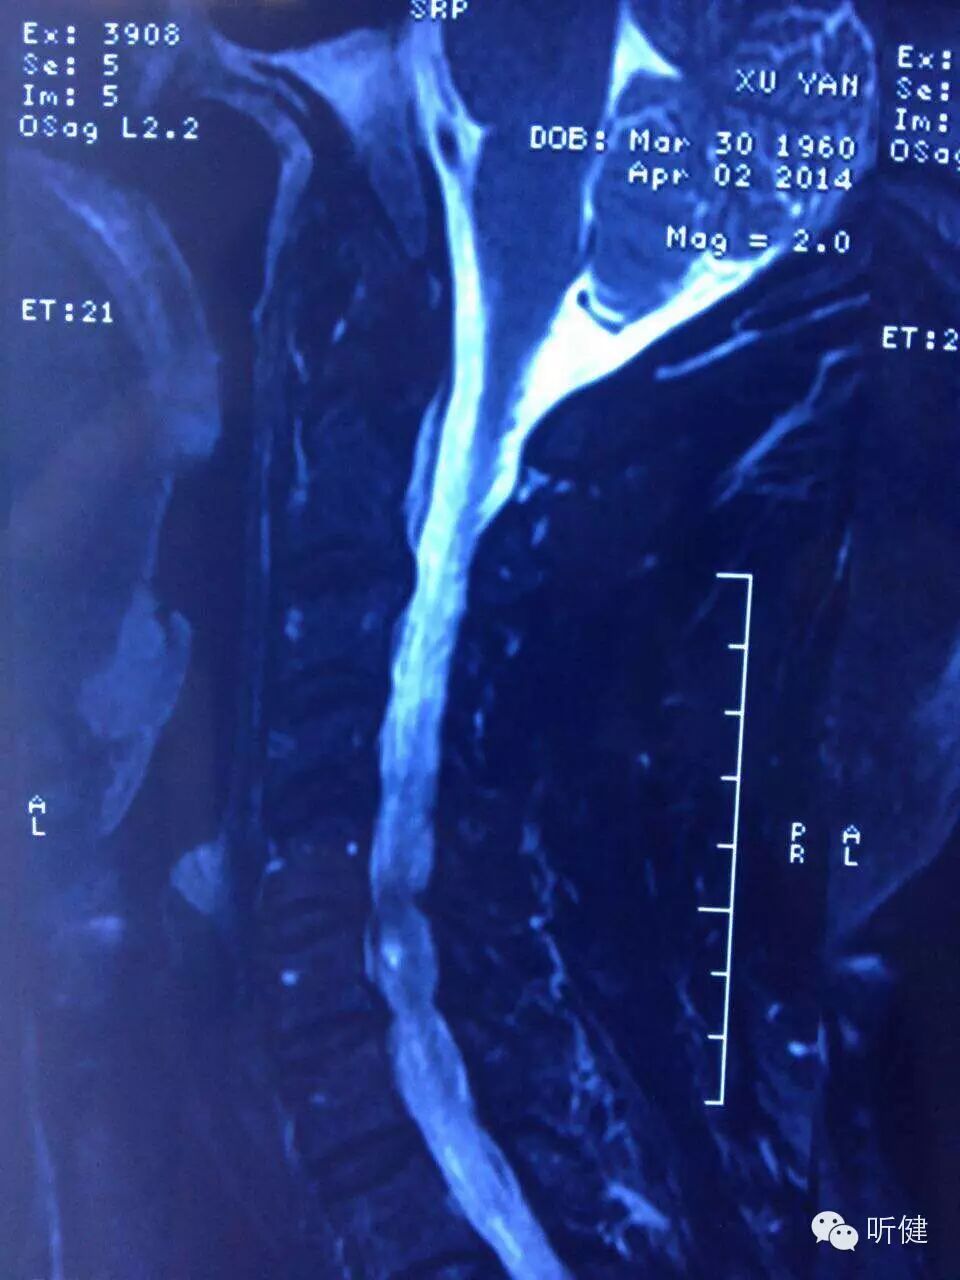

(二)颈椎及椎间盘退行性变引起椎间孔狭窄

椎间孔的大小和形状,在很大程度上取决于椎间盘的完整。当椎间盘突出时,无论在静态或动态下,都能影响相邻椎骨各部分之间的相互关系,并改变椎间孔的大小和形状。此时,椎间孔内通过的神经和血管,都可因压迫、牵拉、成角和炎症而受到刺激。

(三)颈椎间盘退行性变、突出引起的非菌性炎症

颈椎间盘退行性变、突出,椎间盘物质释放可直接引起非菌性炎症、水肿; 引起颈椎间盘源性神经根炎。除了直接产生疼痛外,末梢释放炎性介质,引起分布区域内软组织炎症也可产生疼痛,这是部分患者发生顽固性颈源性头痛的机制。